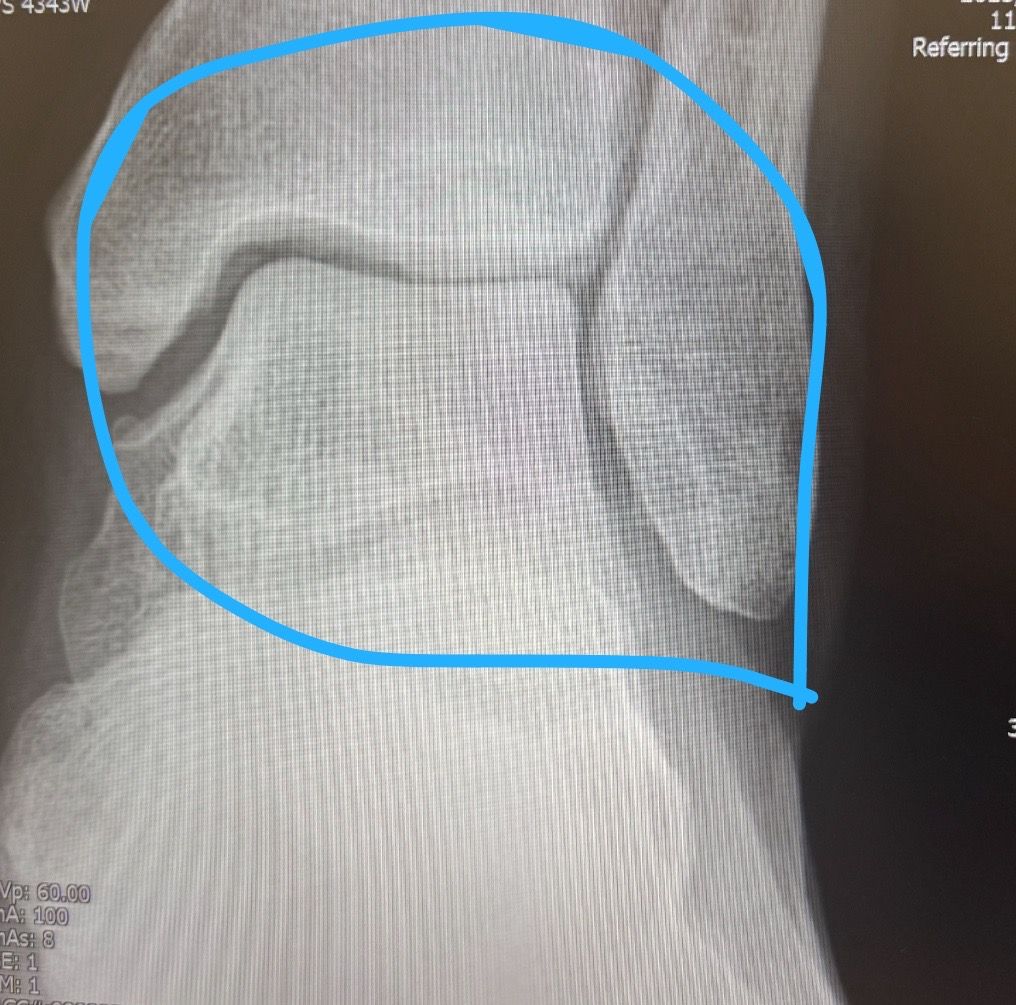

혹시 발목 관절염 초기 맞는지 엑스레이 사진 올려봅니다.

파란원 좌측 발목 (관절염)

엑스레이 상 좌측 발목은 관절 간격이 좁아지고 연골 손상 소견이 보여 초기 발목 관절염 가능성이 높습니다. 오래 성 있거나 뛸때 통증이 있는 것도 관절염의 전형적인 증상 중 하나입니다.

사진으로 올려주신 양쪽 발목의 x-ray를 비교했을 때 통증이 있으신 쪽의 사진이 상대적으로 관절의 공간이 좁아 보이는 경우에는 발목 관절염을 의심할 수 있는데요, 발목관절염의 의심소견이 있는 경우에는 주치의와 상담하여 정밀검사를 고려하시거나 치료 및 재활을 고려해보시는 것을 추천드립니다.

위쪽 면이 살짝 좁아진것같기는 하지만 증상이 없었다면 그냥 넘어갈 수 있을 정도로 경미합니다. 골극도 보이지 않구요.